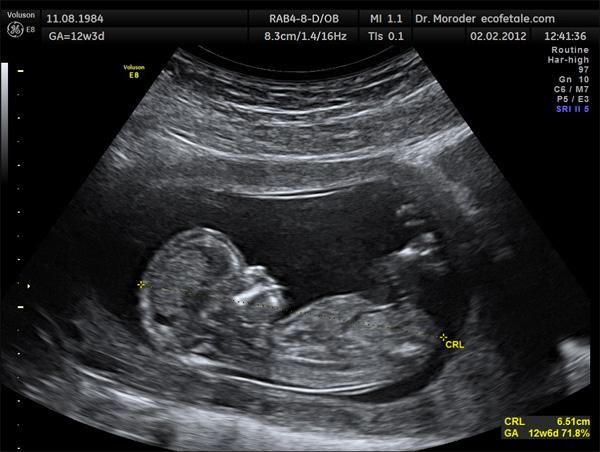

Thông thường, ở tuần thứ 4 của thai kỳ, mũi bé bắt đầu hình thành như một phần đường thở của bào thai. Tới cuối tam cá nguyệt đầu tiên, tức tuần thai thứ 11, các thành phần cơ bản của mũi đã hình thành. Chính vì thế ở thời điểm này, các mẹ bầu nên đến bệnh viện để tiến hành siêu âm kiểm tra chiều dài xương mũi.

Chiều dài xương mũi là một trong những chỉ số phát triển quan trọng ở thai nhi mẹ cần quan tâm. (Ảnh minh họa)

Giai đoạn tuổi thai vào tuần thứ 17, 18, 21, 23, 25, 27 hay các tuần thai của 3 tháng giữa thai kỳ, mẹ bầu sẽ được bác sĩ tiến hành làm xét nghiệm chiều dài xương mũi thai nhi.